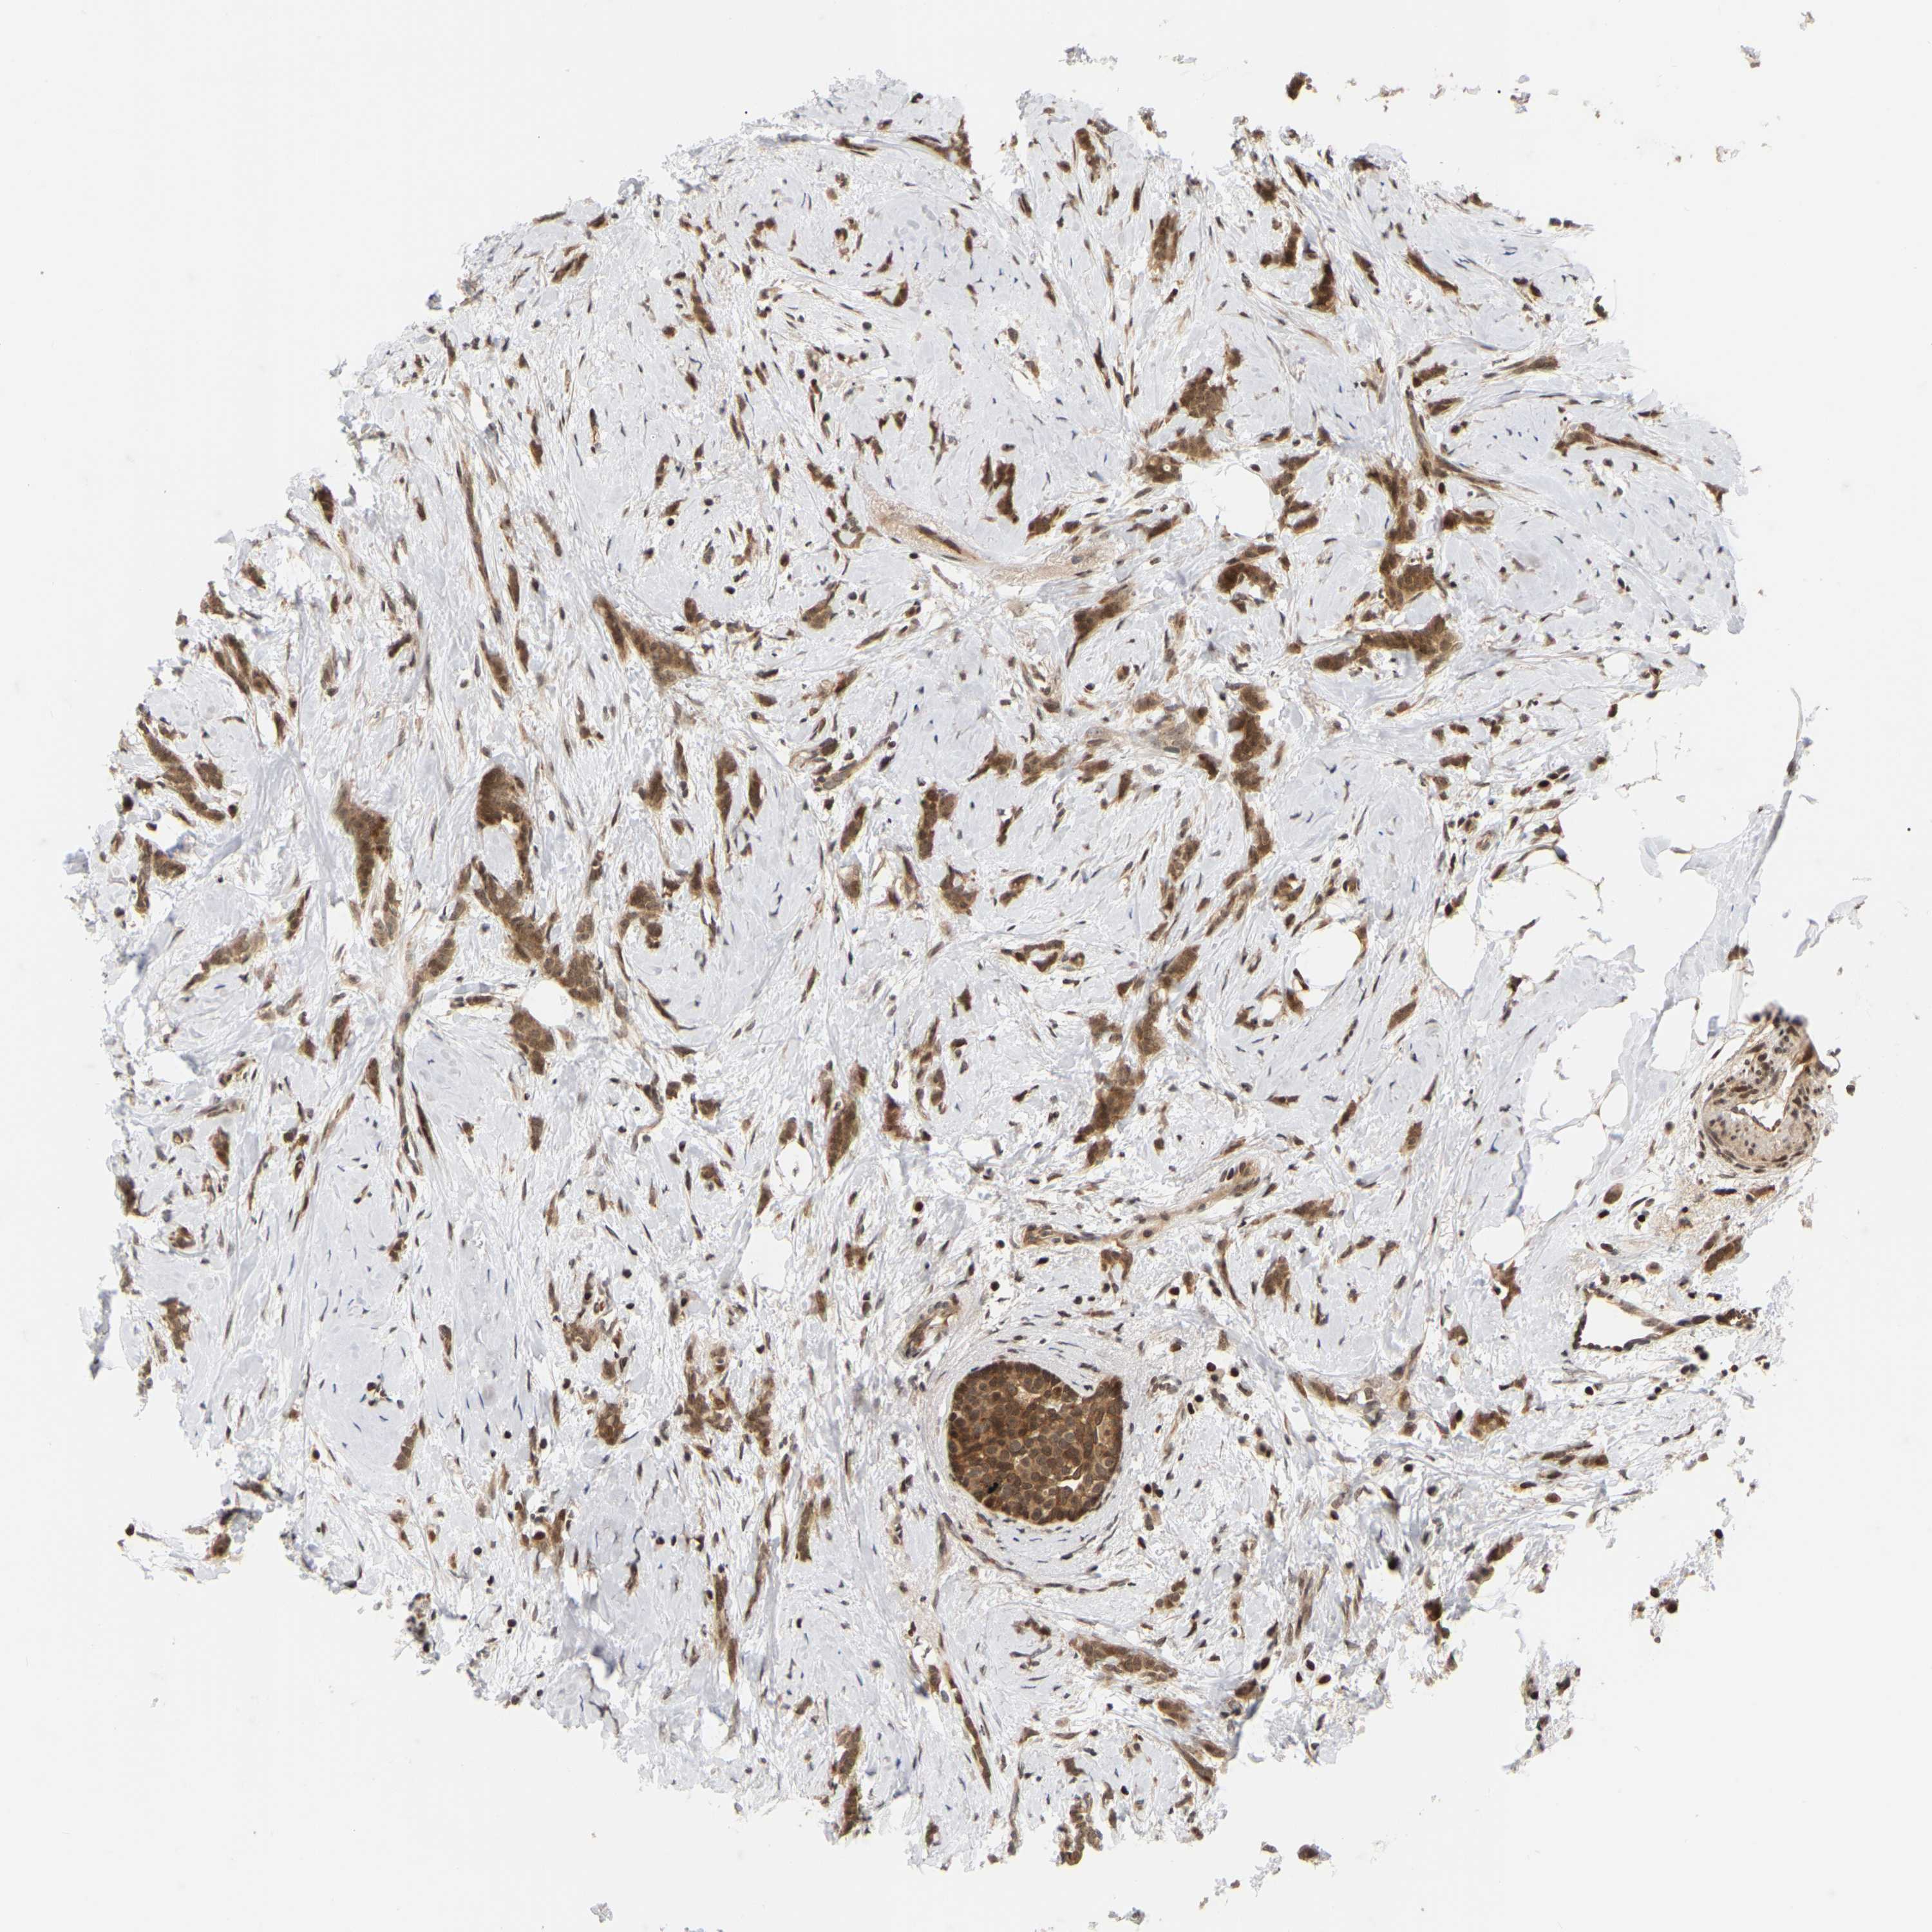

• NFE2L2

CANCER BREAST CANCER Show tissue menu

Breast cancer

Human cancer

NFE2L2 is not prognostic in Breast Invasive Carcinoma (TCGA)